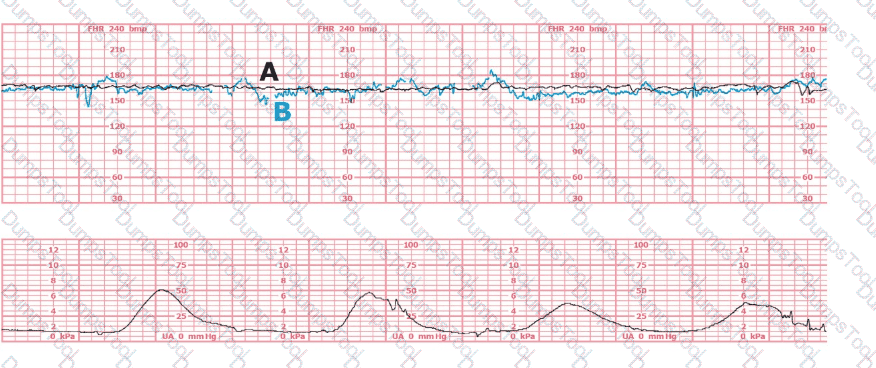

The black pattern represents the heart rate pattern for Baby A. The blue pattern represents the heart rate pattern for Baby B. A possible etiology of the baseline fetal heart rate of Baby A is: